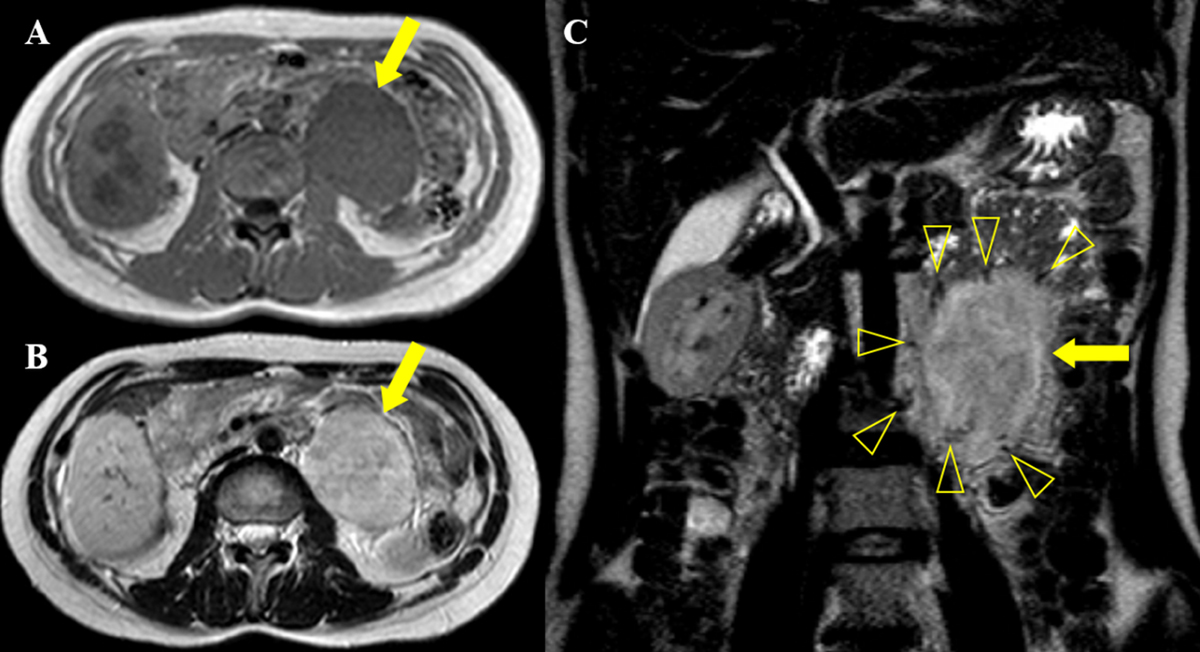

A 30-year-old female was admitted to our hospital after an elevated carbohydrate antigen (CA 19-9, 42.1 U/ml) was discovered on a health check-up. Her past medical history was unremarkable. Contrast-enhanced computed tomography (CT) was performed to check for abdominal malignancy. Axial and coronal reformatted arterial phase CT images (Figure 1A, B, C) showed an 8 cm, avidly heterogeneous enhancing mass (arrow) below the left kidney (open arrow). Left hydronephrosis (open arrow) occurred as the mass (arrow) compressed the left upper ureter. Coronal maximum-intensity projection reformatted CT image (Figure 1D) revealed multiple serpentine arteries (open arrowheads) along the periphery of the mass (arrow). The patient underwent magnetic resonance imaging (MRI) for further evaluation. The retroperitoneal mass (arrow) was iso-intense on T1-weighted image and hyperintense on T2-weighted image, with a well-circumscribed margin (Figure 2A and 2B). Coronal T2-weighted image revealed multiple signal voids (open arrowheads) along the periphery of the mass (arrow), a finding that suggests the vessels (Figure 2C). Axial dynamic gadolinium-enhanced T1-weighted images demonstrated the mass (arrow) with heterogeneous and strong enhancement on the arterial phase (Figure 3A and 3B) and prolonged enhancement on the portal venous and three-minute delayed phase (Figure 3C and 3D). The patient underwent mass excision and left nephrectomy, and she was diagnosed with retroperitoneal solitary fibrous tumor (SFT).

Figure 2